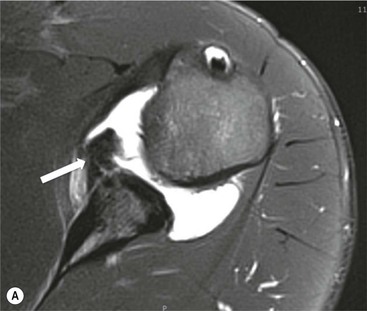

Tears of the superior labrum and biceps anchor are commonly encountered injuries in overhead throwing athletes. Abnormal traction on the biceps anchor and superior labrum results in tears that usually extend posteriorly. They are often referred to as superior labral tears anterior to posterior (SLAP tears).7 MRI, MR arthrography or CT arthrography may assess the glenoid labrum.

Contrast medium or fluid signal intensity extending into the substance of the labrum or through the chondro-labral junction is the primary sign of a SLAP tear (Fig. 46-13). Tears may be localised to the posterosuperior labrum, or may be more extensive. There may be tear extension into the LHB tendon. There are many grades of SLAP tears described but the extent of the tear and the structures involved are the most important features.8